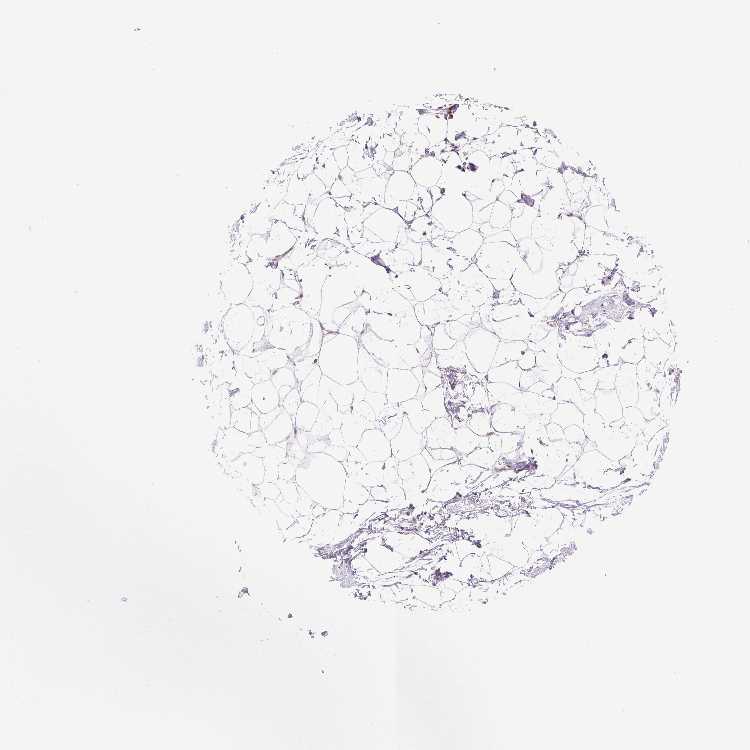

BREAST - Antibody stainingi

Antibody staining in the annotated cell types in the current human tissue is reported as not detected, low, medium, or high, based on conventional immunohistochemistry profiling in selected tissues. This score is based on the combination of the staining intensity and fraction of stained cells.

Each image is clickable and will lead to virtual microscopy that enables deeper exploration of all samples and also displays staining intensity scores, fraction scores and subcellular localization as well as patient and tissue information for each sample.

Antibody HPA055678

Adipocytes Medium

Glandular cells Medium

Myoepithelial cells Medium